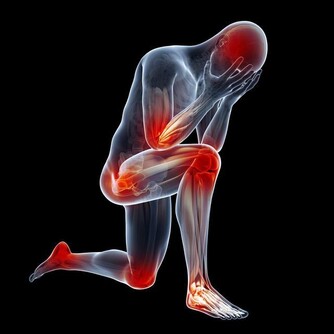

人的身體受到碰撞後,偶爾就會因為小靜脈或微血管破裂而造成瘀青,一般來說碰傷的瘀青在7天內就會恢復原樣;但如果你在這段期間有仔細觀察的話,就會發現瘀青會轉換成不同的顏色,有時候看起來好像還更嚴重了?!不過在了解身體在處理瘀青的過程後,你就能知道這到底是怎麼回事! 1. 紅色

紅色的瘀青代表了很新鮮的瘀傷。瘀傷有時候只要花數分鐘至一兩天便可以完全痊癒,復原的速度根據你出血的位置多深。會出現紅色是因為新鮮的血液從破裂的血管流到了組織,鐵、氧含量高的新鮮血液還呈現紅色所致。 2. 藍色

有時候你的瘀青會在短期間內改變它的顏色,因為從血管流失的血液氧含量迅速減低,血液顏色就會不斷變暗,最後會呈現深藍並帶點紫色。如果你碰傷的血管是在肌膚的更裡層,瘀青甚至會跳過紅色的階段,讓你在皮膚上跑出藍紫色的痕跡。 3. 紫色

紫色的瘀青在外觀上跟成因上都跟藍色極為相似,狀況大概都會維持1-3天。如果顏色越鮮明、濃烈的話就代表內部傷得越深,甚至還有可能會出現黑色。在這個時期,身體會快速地製造出新的紅血球,將它運輸到受傷的部位。 4. 綠色

瘀青過了幾天後會轉變成綠色,紅血球在破裂後會產生血紅蛋白,而癒合階段中身體會把血紅蛋白轉變成新的化學物質,因而改變了它的顏色。這個階段的瘀血常常以綠色為中心,外圍繞著藍紫色的邊界。 5. 黃色

瘀青呈現黃色的時候,就是它快好啦!在這個階段,大部分的血紅蛋白都已經被分解完畢,變成了膽紅素,這會使皮膚表層看起來像黃色。而在這個最終階段里,身體還在清理那些從血管漏出來的細胞,清完後瘀青就徹底康復! 雖然在大多數的狀況下,瘀青都會透過上述的那些階段自己進行癒合,所以人類其實不太用去管它;但如果想減少一些疼痛或腫脹,或讓它好得更快,也是有其他辦法的喔!不過常有人說的「去揉它就會很快消掉」是錯誤的!因為隨意亂揉的話可能會造成血管破裂更加嚴重,讓瘀青顏色加深喔! 解決方法一:敷冰袋 在瘀青的地方敷上冰袋或其他冰凍的東西,就可以有效解除疼痛或腫脹。一天約敷三次,每次以10-20分鐘為限。 解決方法二:抬高患處 將瘀青的部位抬高到超出心臟的水平,然後同時敷冰袋,可以減少出血的面積。 解決方法三:在兩三天後進行熱敷 在剛受傷的48小時內,儘量避免浸泡熱水、用熱水淋浴、熱敷,或是喝下太多的酒精。但再過兩天後,如果大部分的腫脹已經消失了,就可以開始對傷處進行熱敷,跟冰敷一樣一天進行三次,每次10-20分鐘。這可以加速血液的流動,並幫助癒合過程。 解決方法四:包裹患處 在瘀青腫脹消失後,你可以開始試著和緩地運動該部位,幫助它恢復彈性。這個階段也可以用彈性繃帶包裹患處,稍微進行壓縮,但切記不要包得太緊,以免又回復成腫脹的狀態。一但覺得有點發麻,就要把繃帶放鬆一點。 解決方法五:塗抹外傷藥 坊間有不少能夠治療瘀傷的藥品,選擇天然的藥物,例如含有金縷梅或山金車的藥,就能夠幫助傷口復原。 如果想要讓身上的瘀傷快點消失,就可以嘗試以上的方法,放著不管的話,瘀傷通常也會在7日內消失。但如果7天後瘀青沒有消失,顏色甚至還變深的話,就要考慮去看醫生,因為這時候可能不是單純瘀青,而是其他疾病喔! P/S:據聞,一些瘀青不疼不痛是被「好兄弟」捏的哦…如果你到過一些陰陽的地方,過後有出現這類的瘀青,那就很大可能是好兄弟的傑作。(這是聽說而已…)